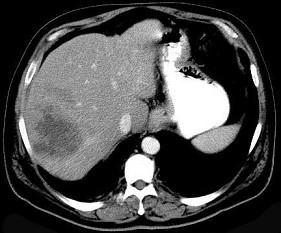

问题 细菌性肝脓肿的最常见致病菌是 ( )

选项 A、粪链球菌、金黄色葡萄球菌和厌氧菌 B、溶血性链球菌、金黄色葡萄球菌和厌氧菌 C、大肠杆菌、粪链球菌和厌氧菌 D、大肠杆菌、金黄色葡萄球菌和厌氧菌 E、大肠杆菌、绿脓杆菌和厌氧菌

答案 D